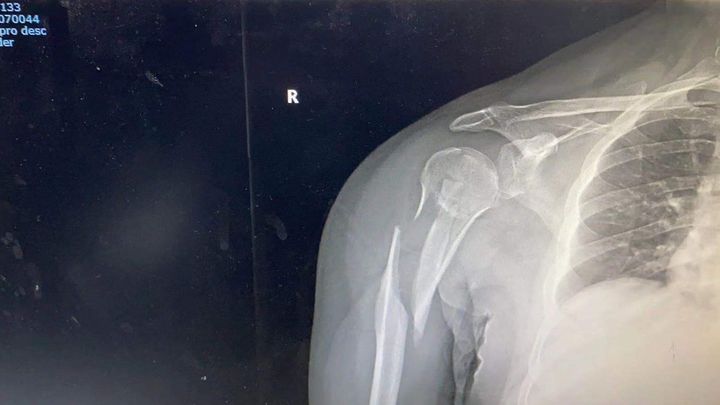

I am in Shanghai China and a hit and run driver accident from rear on my bicycle cause severe break to my right arm. I am a professional drummer but i may not be able to perform for several months. I don’t have insurance and the operation is $10,000.